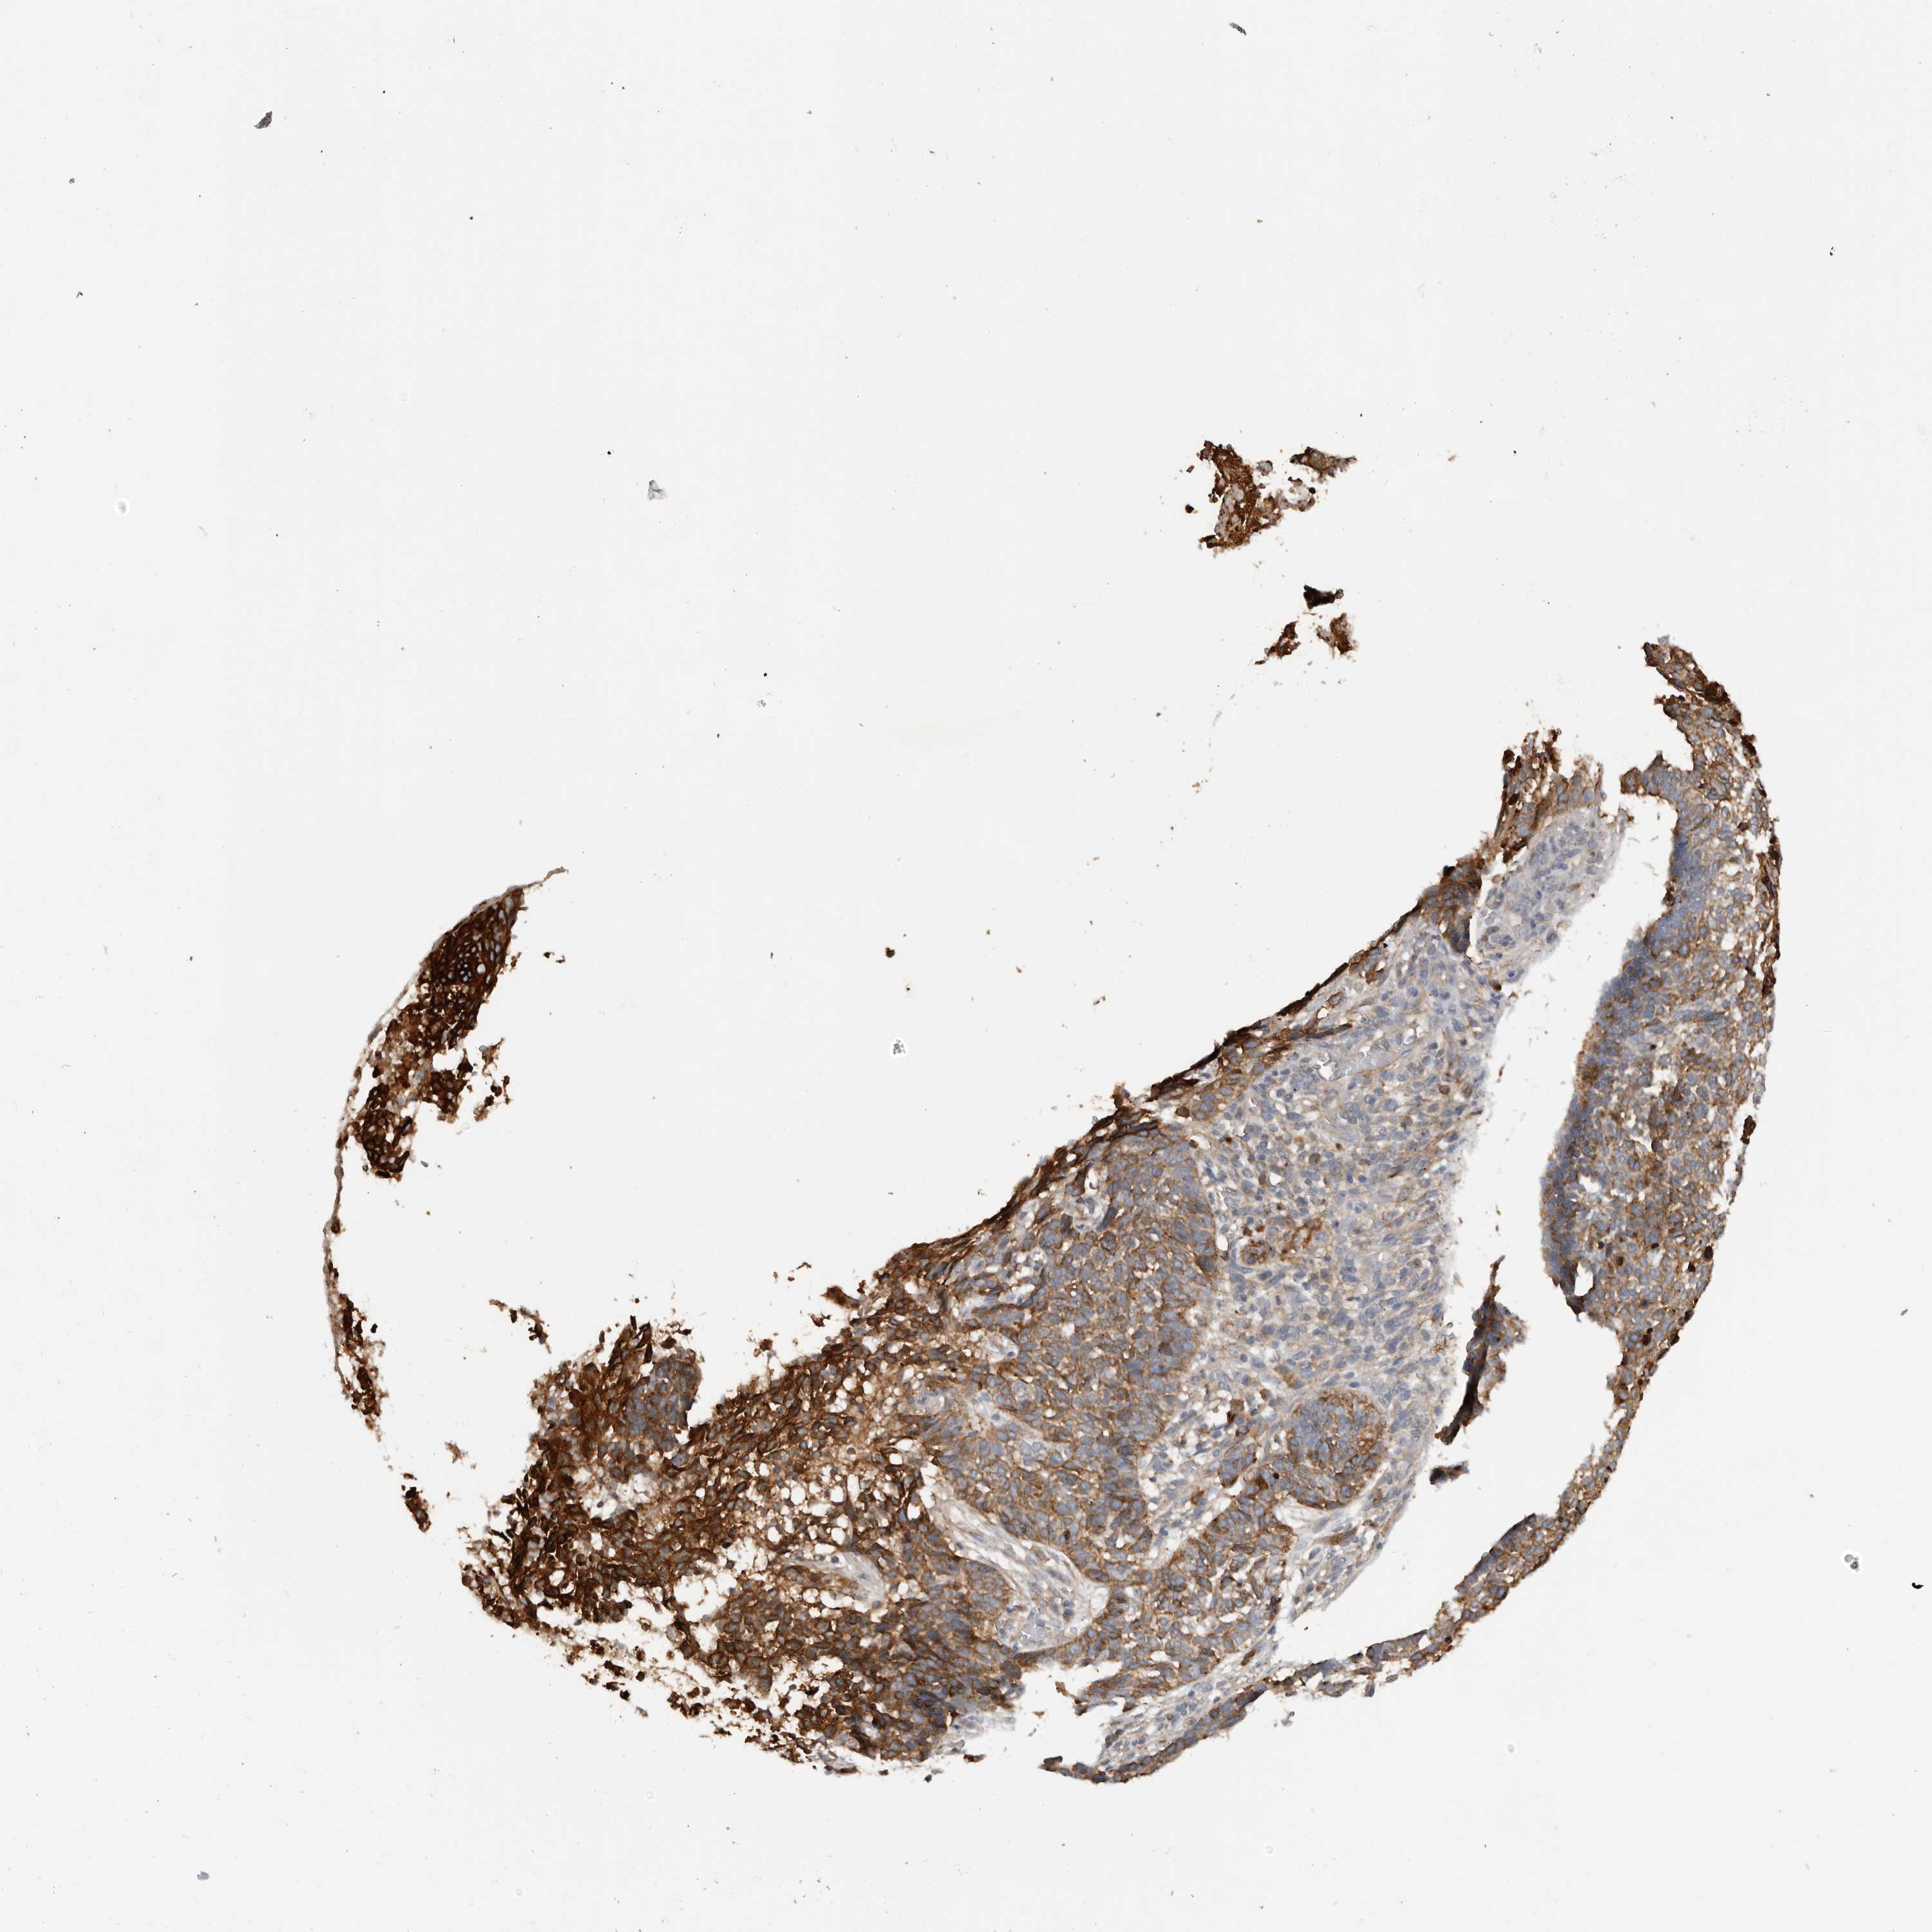

Basal cell and squamous cell cancer

SKIN CANCER - Protein expressioni

A mouse-over function shows sample information and annotation data. Click on an image to view it in a full screen mode. Samples can be filtered based on level of antibody staining by selecting one or several of the following categories: high, medium, low and not detected. The assay and annotation is described here.

Each image is clickable and will lead to virtual microscopy that enables deeper exploration of all samples and also displays staining intensity scores, fraction scores and subcellular localization as well as patient and tissue information for each sample.

Antibody HPA028598

Antibody CAB000153

Basal cell carcinoma

Squamous cell carcinoma, NOS

Squamous cell carcinoma, metastatic, NOS